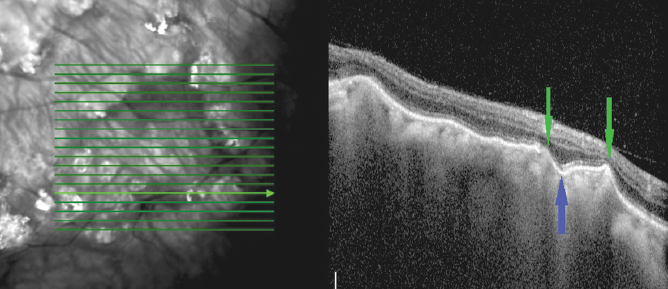

In our cases, the acquired tomographic signs were characteristic of SCC, namely the chorioretinal complex elevation with an uneven tuberous surface, the presence of a “peak-shaped” contour of the Bruch’s membrane, a choroid thinning with increased signal hyperreflectivity, the presence of damage zones in the Bruch’s membrane, disorders of the retinal architectonics (thinning due to atrophy of the retinal outer layers in the zones of the Bruch’s membrane “peak-shaped” contour and an increase in the retinal thickness because of expansion of the nuclear layers in the Bruch’s membrane retraction zones) (Figs. 3, 4). Under the thinned choroid, zones of a local moderately hyporeflective structure were visible (Fig. 5), which is considered as a distinct sign of scleral inner layers lesions [3]. Furthermore, the visualization of the outer border of the choroid was disturbed in the areas of the retinal lesion.

Fig. 4. Optical coherence tomography of the patient T. (64 years old). Horizontal scan across sclerochoroidal calcification. Arrows – area of retinal damage, visualization of the outer border of the underlying choroid is impaired

Рис. 4. Оптическая когерентная томография пациента Т., 64 года. Горизонтальный срез через нижнюю часть очага. Стрелки — зона повреждения сетчатки, нарушена визуализации наружной границы подлежащей хориоидеи